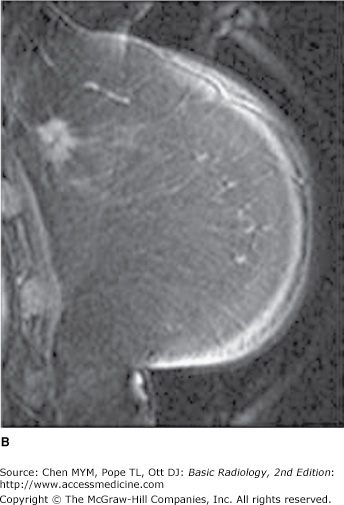

A) Mammogram showing dense breast tissue. (B) MRI of same breast showing enhancing cancer in otherwise minimally enhancing breast.